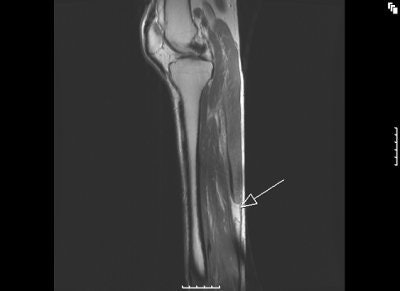

![]() |

MR images of the tennis leg injury sustained by Mintz. Above, a coronal fat-suppressed image through the back of the calf with the arrow pointing to the muscle tear. The hematoma is tracking up the leg. Below, sagittal MR of the whole calf. Arrow points to the muscle tear and the white below it is the gap from the muscle retraction. Images courtesy of Dr. Douglas Mintz.